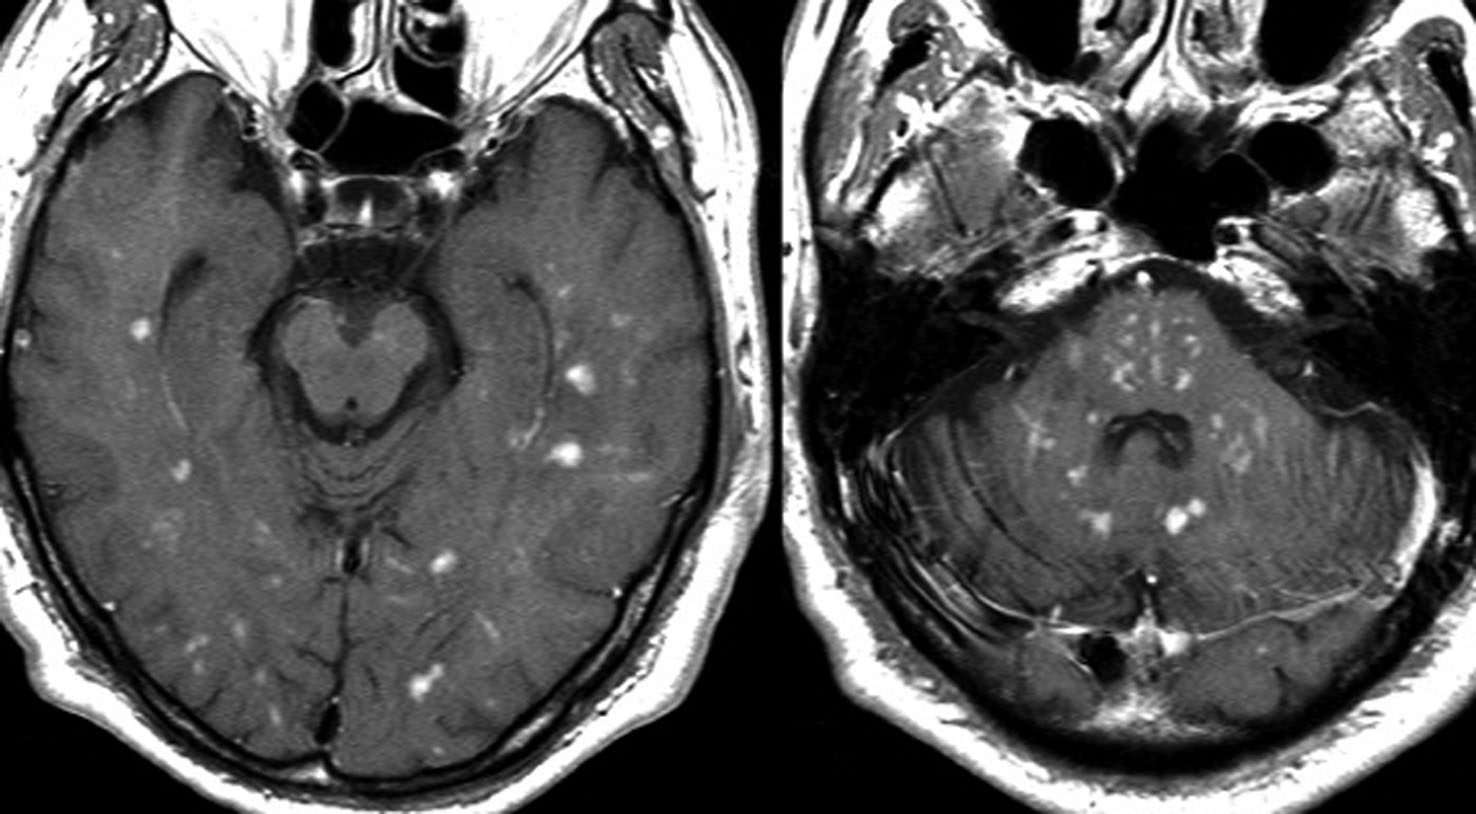

MRI検査で,はっきりわかります。MRI造影剤を入れると均一または斑らに増強(真っ白になる)されて(左側),周囲には脳の腫れ(脳浮腫)がみられます(右側)。できやすい場所は側脳室の周囲・大脳脳基底核・小脳・脳幹部など脳の深いところ(深部白質)です。脳の中に2個以上のリンパ腫が同時にできる多発例というのもしばしばあります

これは1990年代の古い例ですがリンパ腫の増大が早いことをお見せします。左側のはTHP-COPという化学療法をする前のものです。真ん中のは化学療法から4日目で,腫瘍は小さくなりました。でも,2コース目の化学療法の直前(4週間後)にもう一度MRIをしてみたらすごく大きくなっていました。この化学療法は効いているのだか効いていないのだか判らないことになります。化学療法を行なうならとても強い薬剤を使わなければなりませんし急がなければなりません。